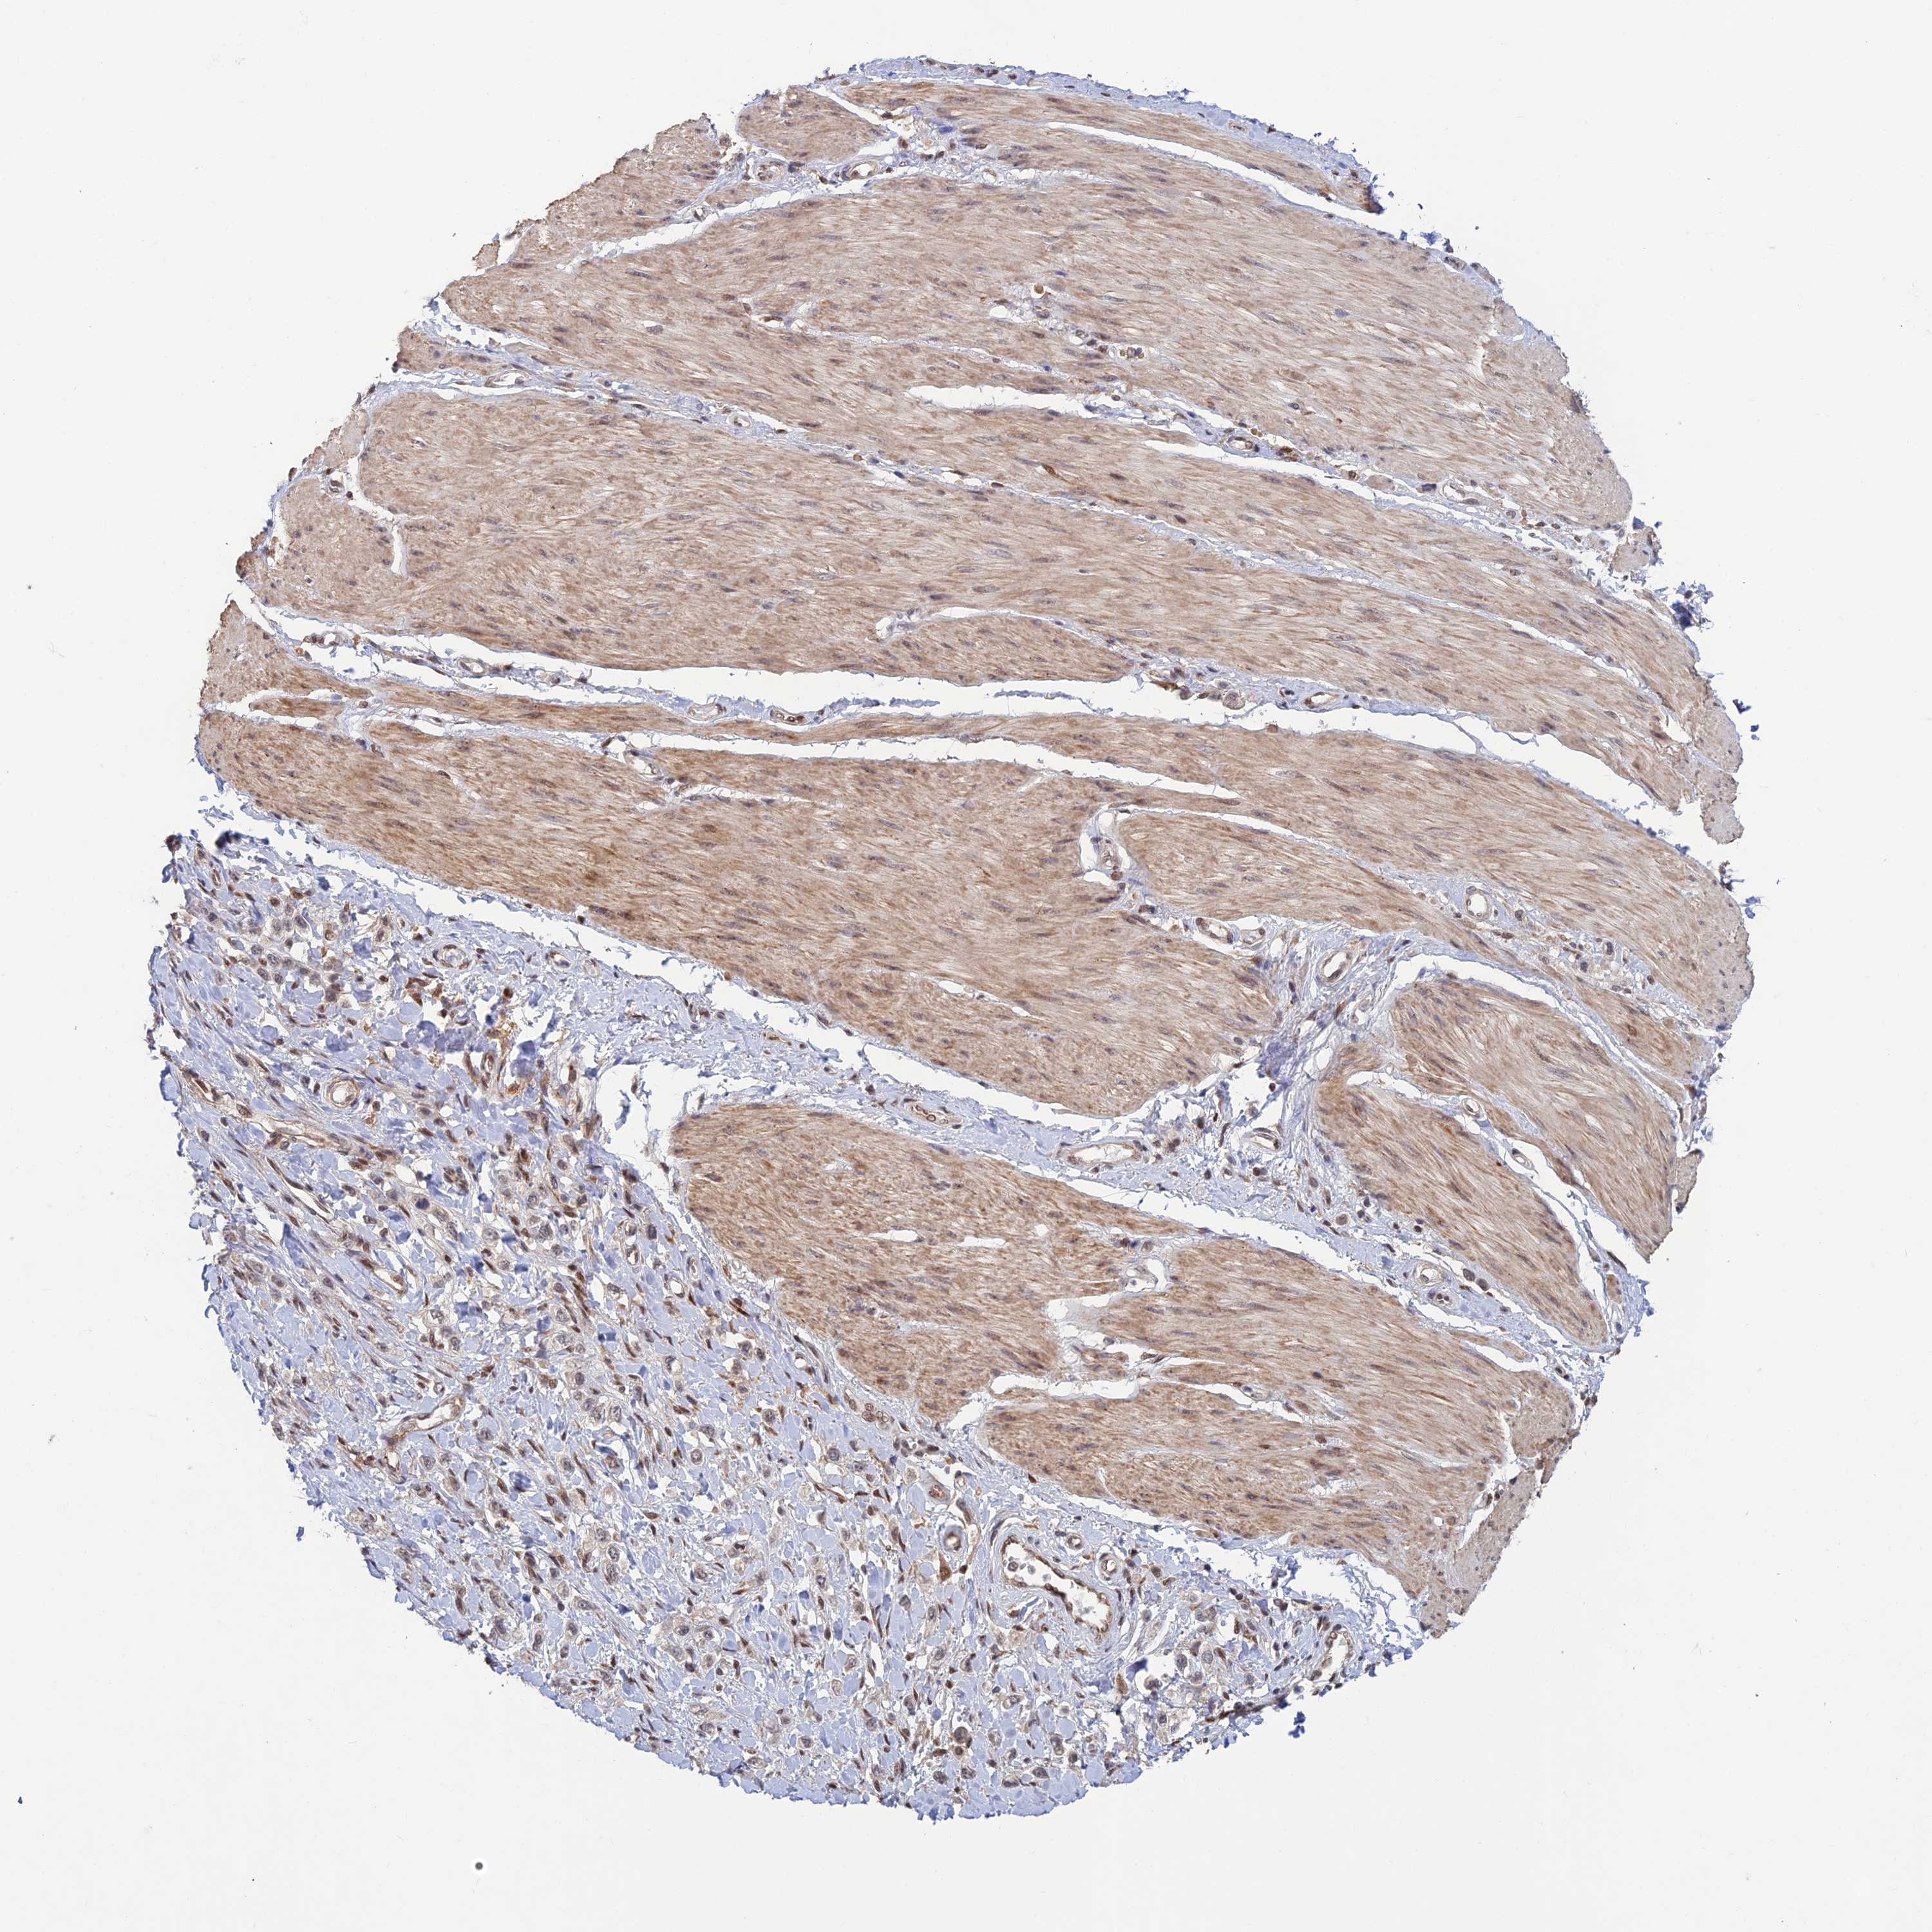

STOMACH CANCER - Protein expressioni

A mouse-over function shows sample information and annotation data. Click on an image to view it in a full screen mode. Samples can be filtered based on level of antibody staining by selecting one or several of the following categories: high, medium, low and not detected. The assay and annotation is described here.

Note that samples used for immunohistochemistry by the Human Protein Atlas do not correspond to samples in the TCGA dataset.

Antibody stainingi

Antibody staining in the annotated cell types in the current human tissue is reported as not detected, low, medium, or high, based on conventional immunohistochemistry profiling in selected tissues. This score is based on the combination of the staining intensity and fraction of stained cells.

Each image is clickable and will lead to virtual microscopy that enables deeper exploration of all samples and also displays staining intensity scores, fraction scores and subcellular localization as well as patient and tissue information for each sample.

Antibody HPA044123

Staining

High

Medium

Low

Not detected

Intensity

Strong

Moderate

Weak

Negative

Quantity

>75%

75%-25%

<25%

None

Location

Nuclear

Cytoplasmic/membranous

Cytoplasmic/membranous,nuclear

Adenocarcinoma, NOS